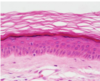

Explain how you would distinguish between thick and thin skin?

Thick skin

- lacks hair follicles

- nasal planum, footpads

- has both stratum lucidum and stratum corneum layers

Thin skin

- most frequent and is usually haired

- no strtum lucidum

Identify all five layers of the epidermis ?

- Stratum basale

- Stratum spinosum

- Stratum granulosum

- Stratum lucidum

- Stratum corneum

Describe and identify the Stratum Lucidum ?

Stratum Lucidum

- contains a protein which has a different staining affinity

- above granulosa layer, only in thick skin

- flattened dead cells of poor staining quality

Identify the five skin layers in a dogs paw pad, what characteristics make this thick skin ?

Dog paw pad

This is thick skin as it has an incredable thick keratinous layer composed of stratum lucidum and stratum corneum (usually lacks hair follicles)

yellow = stratum basale

blue = stratum spinosum

green = stratum granulosum

purple = stratum lucidum

orange = starum corneum